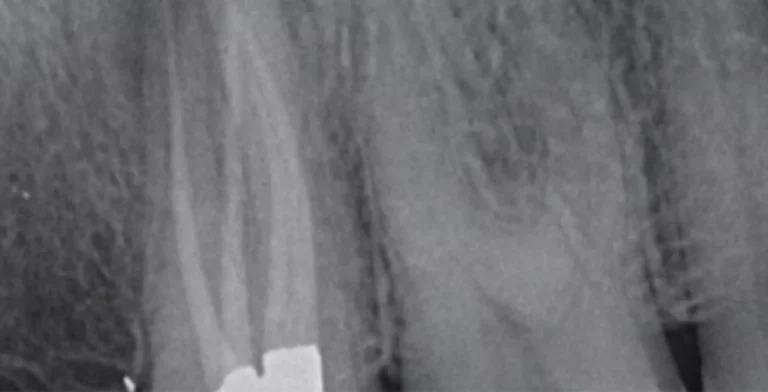

endo-ba04-before-treatment-vitrin-clinic endo-ba04-after-treatment-vitrin-clinic

endo-ba03-before-treatment-vitrin-clinic endo-ba03-after-treatment-vitrin-clinic

endo-ba02-after-treatment-vitrin-clinic endo-ba02-before-treatment-vitrin-clinic

endo-ba01-after-treatment-vitrin-clinic endo-ba01-before-treatment-vitrin-clinic